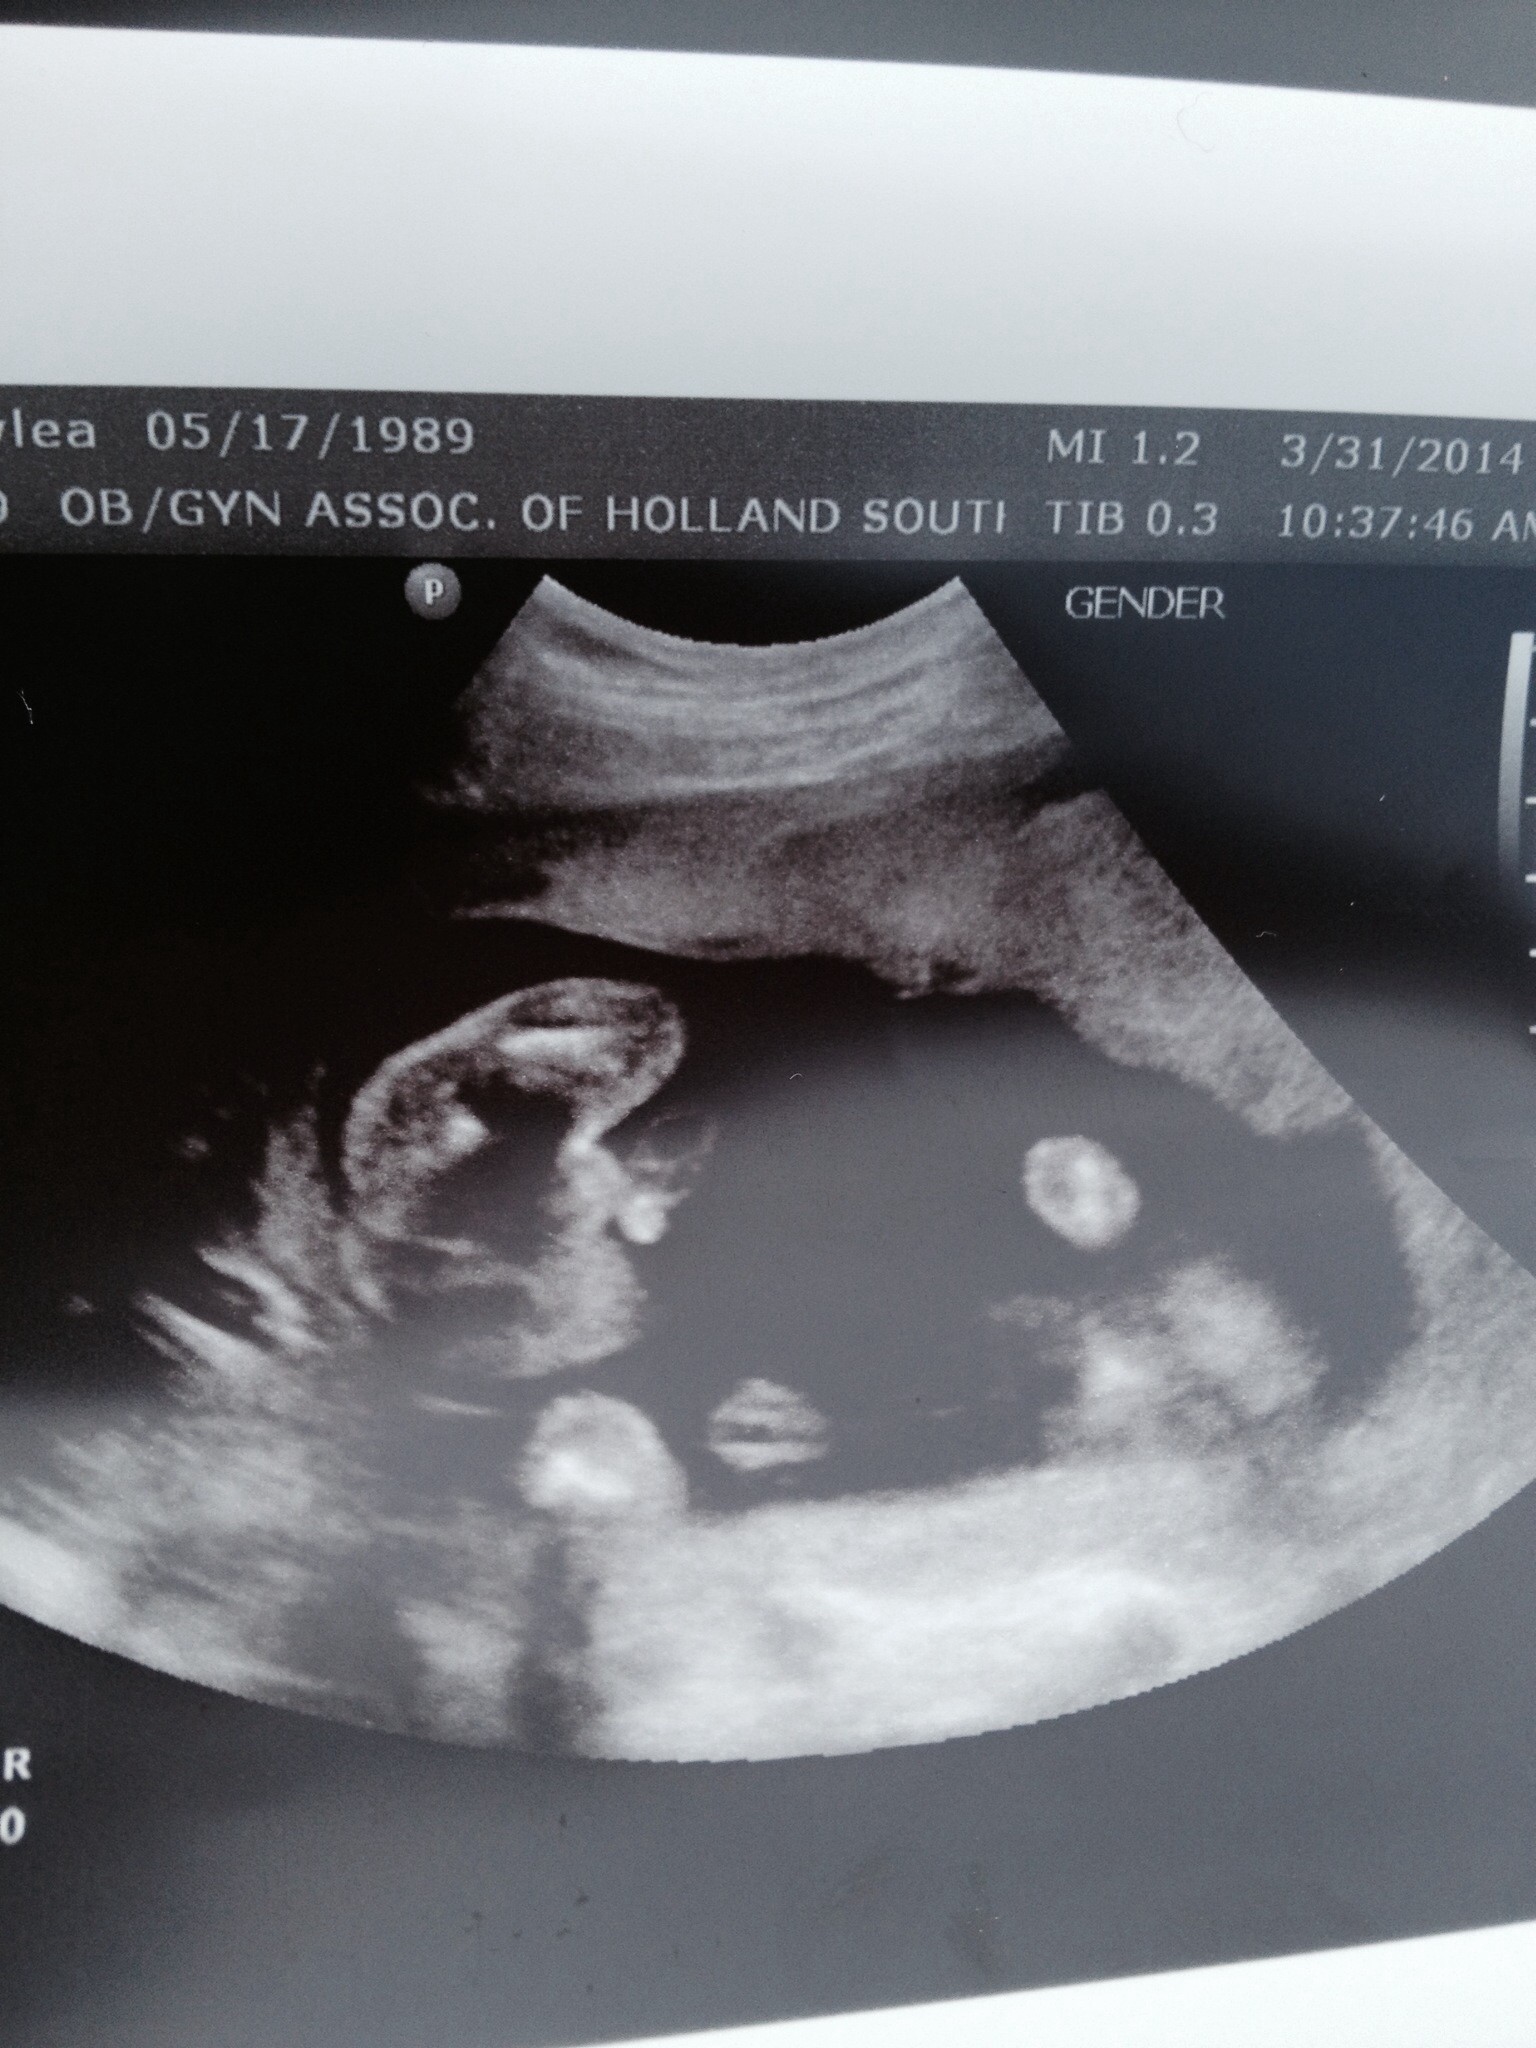

Ok ladies I need some help! Yesterday at our 20 week US baby was in a breach position making it hard for the tech to get a great shot of boy parts. We left the ultrasound with "yeah, I think it's a boy." This is not enough clarity for me!! I'm going nuts! Opinions please! (Buns are on he left side of the screen of this helps)